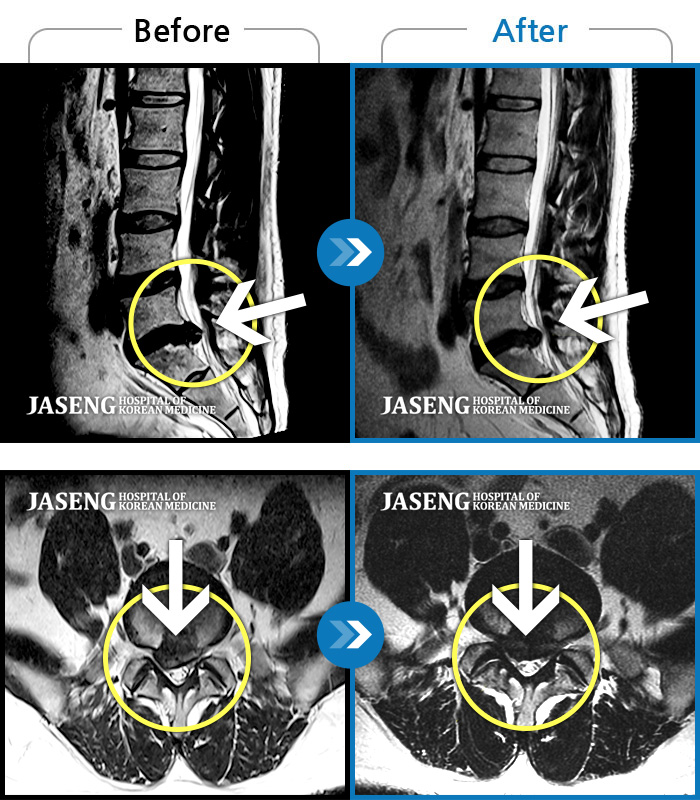

MRI 치료사례

통증 때문에 휴직 후 여러 치료에도 호전이 없던 다리 통증 및 저림